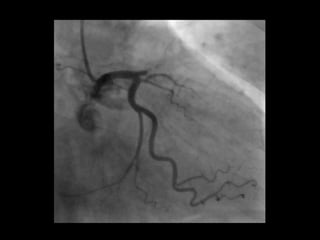

56 Jahre, weiblich

Seit 3 Tagen Herzschmerzen, zuletzt auch in Ruhe

Cholesterin

Familiäre Belastung

Übergewicht

Troponin T hs 67 pg/ml [0 -14]

EKG

Kardinal Schwarzenberg´sches Krankenhaus, Innere Medizin, Freitag 29. Juni 2012

NSTEMI - ACS 56Jahre, weiblich Seit 3 Tagen Herzschmerzen, zuletzt auch in Ruhe Cholesterin Familiäre Belastung Übergewicht Troponin T hs 67 pg/ml [0 -14] EKG Kardinal Schwarzenberg´sches Krankenhaus, Innere Medizin, Freitag 29. Juni 2012